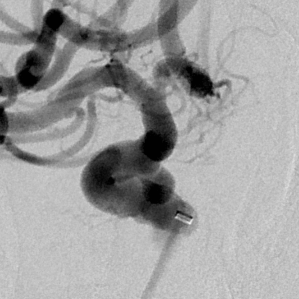

啥也别说了,赶紧去做脑血管造影备治疗吧,结果发现颅内一个炸弹💣(颅内动脉瘤),而且长在一个不太容易破裂的部位(床突旁),形状也不太规则,上面还有一个细长的小泡(破裂点),破裂机制:这个破裂小口,多次小量出血,通过反复的脑脊液循环大部集聚到了腰大池,出现了颅内几乎看不到啥异常而腰大池内为血性不凝脑脊液的巨大反差,血液在蛛网膜下腔进一步刺激神经根,才导致了脖子疼和腰疼~~~,但是,这是脑动脉瘤反反复复破裂出血导致的哦,细思极恐………

这个患者是幸运的,毕竟最后找到了颅内潜伏的炸弹,微创手术顺利拆除,消除了再次出血的风险。